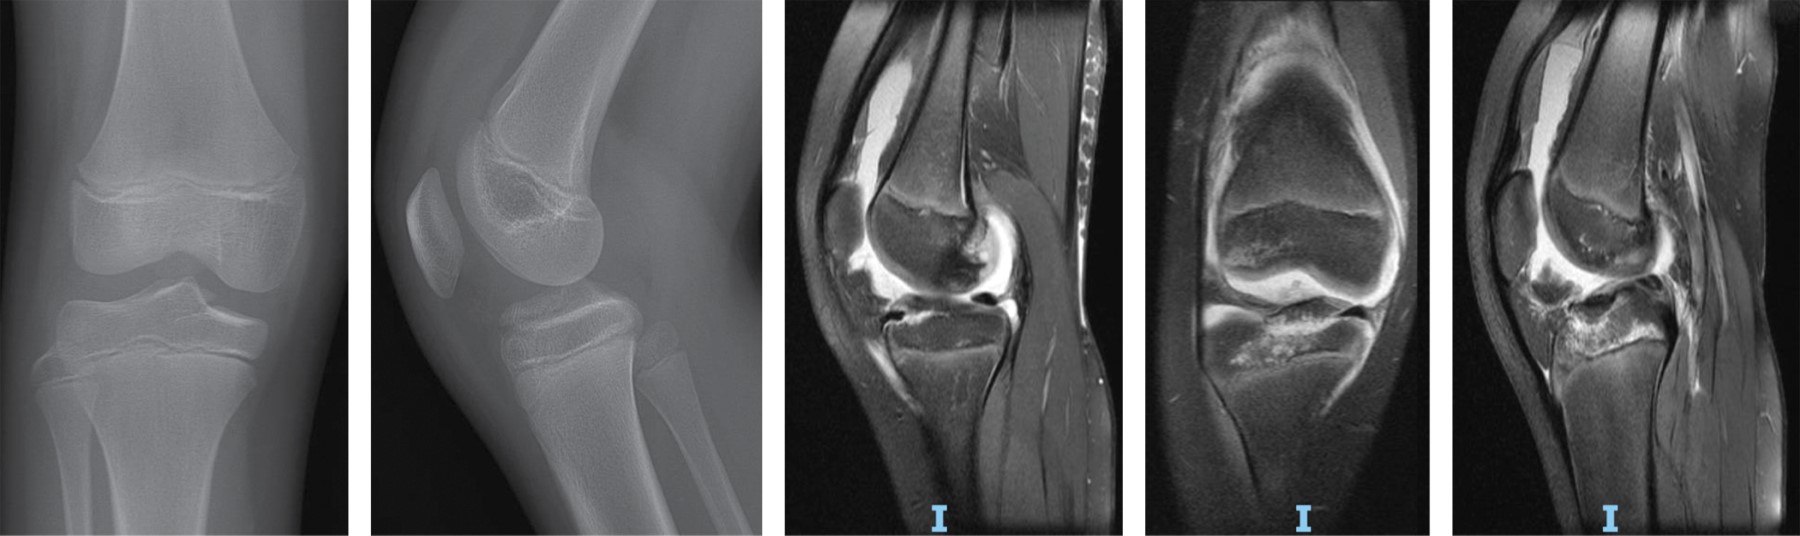

Figure 4